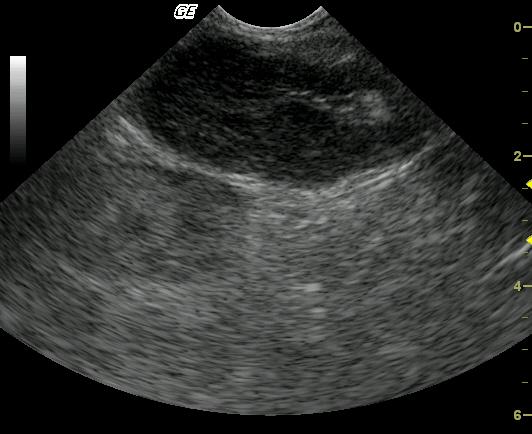

This 3-year-old MN DSH was presented for weight loss. The physical exam revealed hypothermia and palpably enlarged kidneys. A CBC and blood chemistry profile demonstrated severe azotemia that decreased after fluid therapy. Moderate anemia was also present.